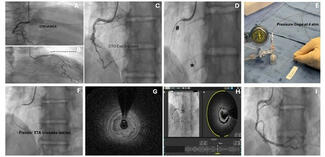

Coronary dissection (46.7%), aortocoronary dissection (26.7%), and coronary perforation (26.7%), including Ellis grade 3 perforations (26.7%), were the predominant indications for emergency cardiac surgery in our cohort. These severe complications can arise suddenly, leading to rapid hemodynamic deterioration through tamponade, myocardial ischemia, or cardiac arrest.19 Our observations parallel those of Darwazah et al, who identified failed angioplasty, dissection, and perforation as the principal drivers of surgical conversion.18 Importantly, while most coronary perforations can be stabilized with covered stents, prolonged balloon tamponade, or pericardiocentesis, a subset remains unresponsive to these strategies and requires immediate surgical intervention.20 An illustrative case from our cohort is shown in Figure 2. This highlights the need for interventional teams to maintain readiness for prompt surgical collaboration when faced with refractory dissection or perforation, as timely escalation can be lifesaving.